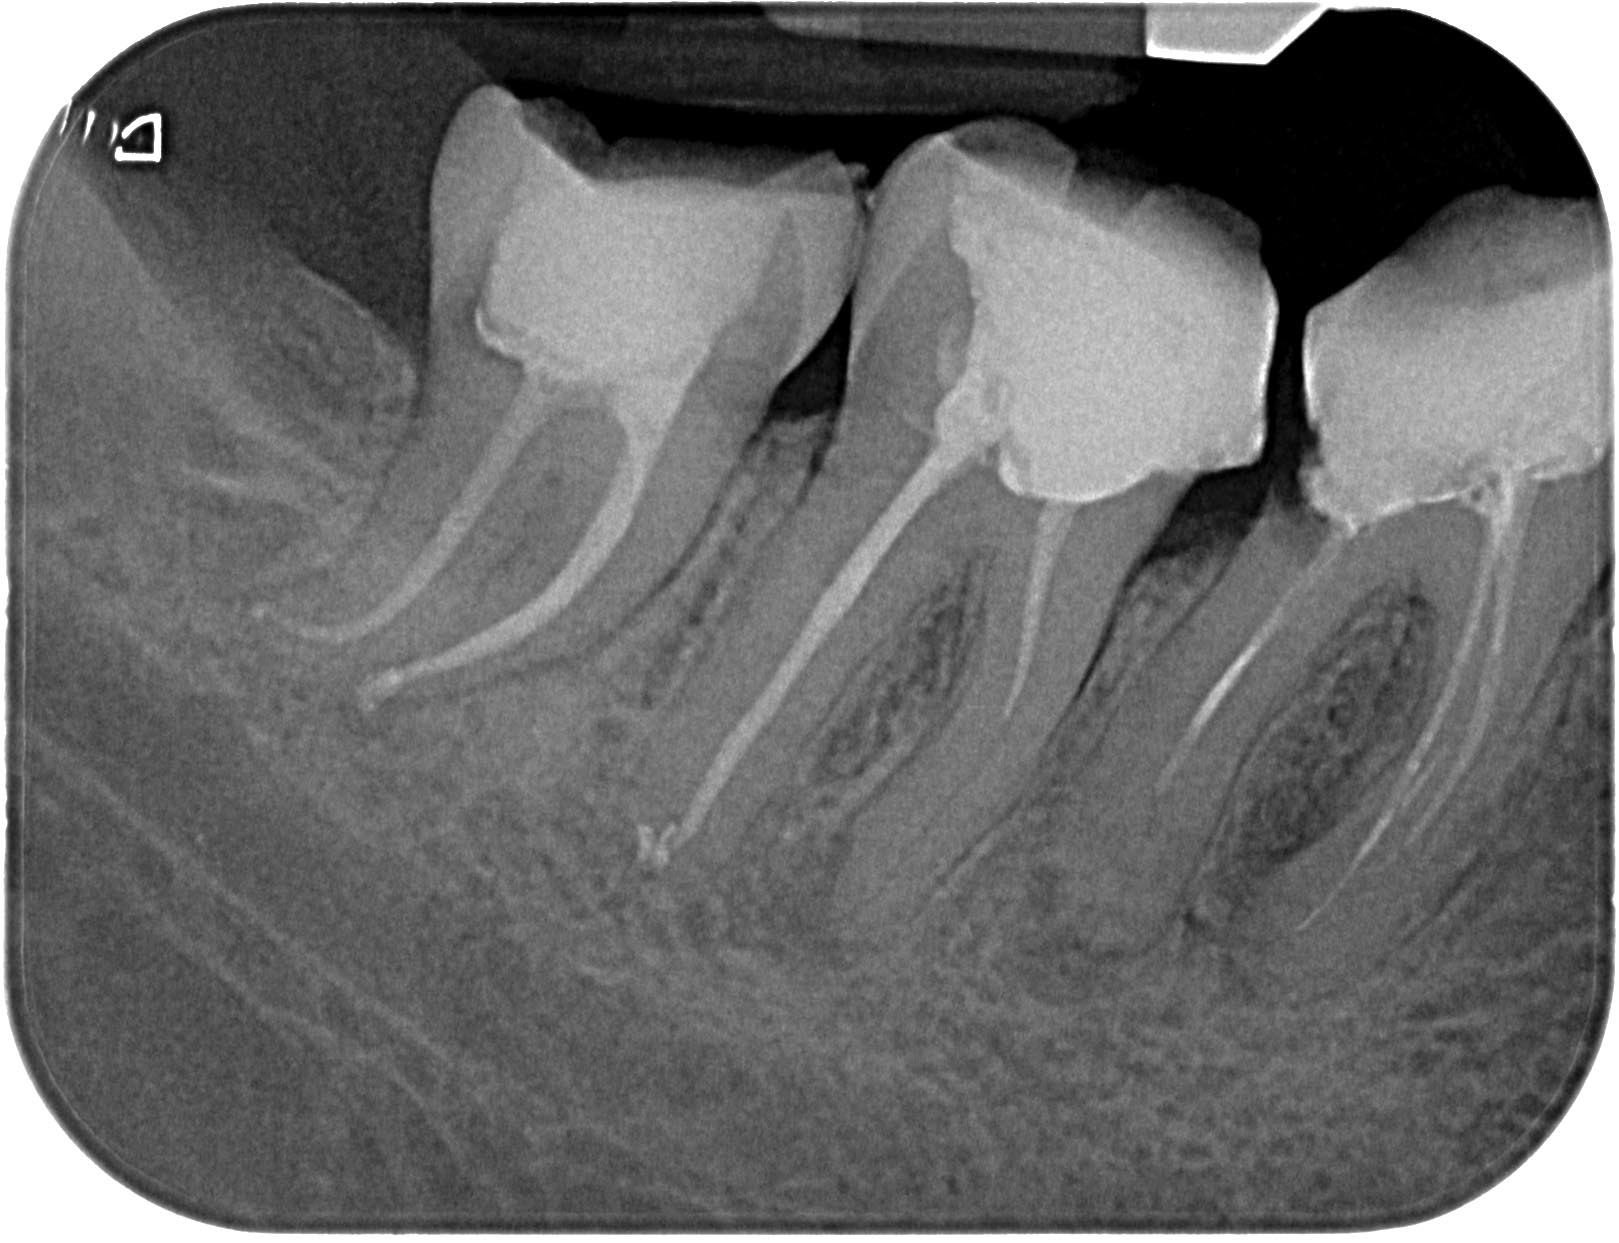

48-1-6 Veröffentlicht 8. Mai 2011 am 1619 × 1243 in Wurzelkanalbehandlung 48 mit RACE 02, MTwo und VDW Reciproc